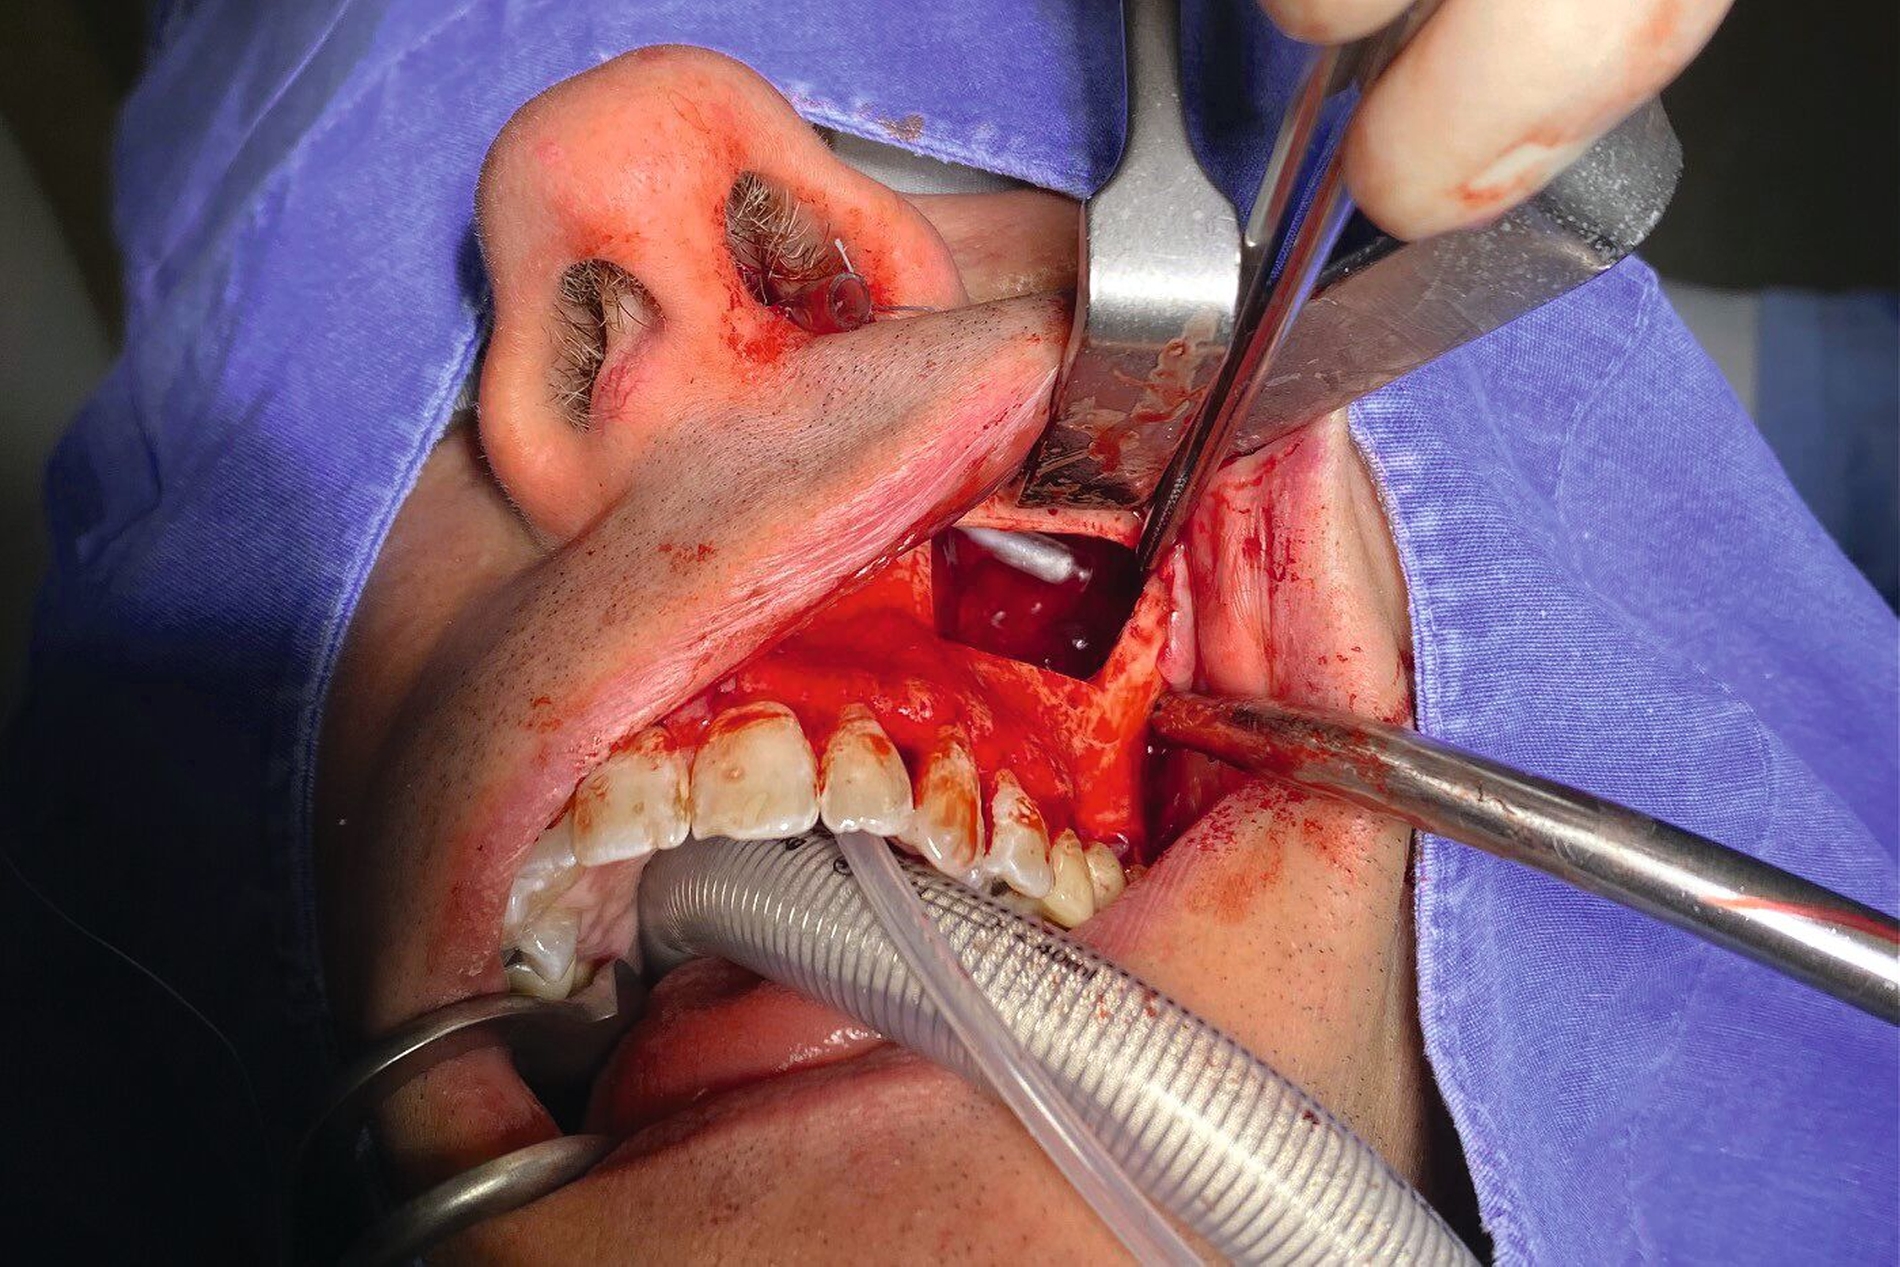

Die Therapie erfolgte in ambulanter Vollnarkose mittels Lindorf-Deckel-Technik. Nach marginaler Schnittführung und Darstellung der Kieferhöhlenvorderwand wurde mittels Piezosurgery ein knöcherner Deckel präpariert und der Sinus eröffnet (Abbildung 3). Es zeigten sich eine große Menge bröckeliges, schwarz verfärbtes Material sowie eine entzündlich veränderte Schleimhaut (Abbildung 4).

Zudem wurde ein Zahnkronenfragment geborgen (Abbildung 7). Die Kieferhöhle wurde unter Erhalt der auskleidenden Schleimhaut vollständig gereinigt und mit physiologischer Kochsalzlösung gespült. Zur postoperativen Spültherapie wurde transnasal ein Drainageröhrchen durch das Ostium naturale eingelegt (Abbildung 5). Auf ein Fenster zum unteren Nasengang wurde daher verzichtet. Der Knochendeckel wurde reponiert und mit resorbierbaren Nähten fixiert (Abbildung 6).